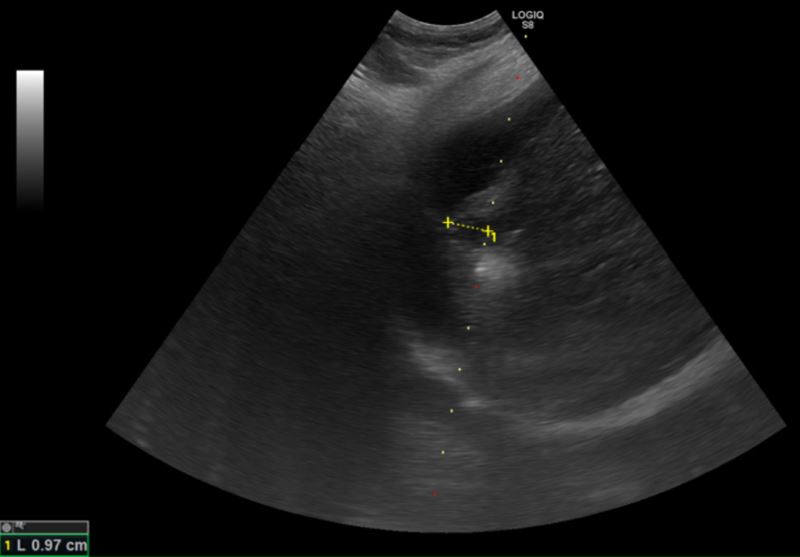

圖為超音波導引下的電燒治療,黃色標記處為肝臟腫瘤,周圍白色處為氣化範圍。(圖/台北慈濟醫院提供)

83歲的黃女士因身體不適到醫院就診,就診過程中意外發現肝功能異常,進一步檢查發現一顆約1.5公分的肝臟腫瘤,確診為第零期肝癌,同時也發現黃女士患有B型肝炎,卻因沒有症狀所以不曾進行相關治療。所幸發現及時,由醫師執行電燒治療,術後三天黃女士順利出院,目前僅需定期追蹤避免復發。

他進一步說明,肝癌患者平均5年的復發率高達七成,因此電燒治療對於可能復發,需要多次治療的患者而言更具優勢,且此療法住院時間短,通常三日左右即可出院。但並非所有個案都適用,治療前需醫師評估凝血功能,若有凝血嚴重異常且無法透過治療矯正者,則不適用電燒治療。